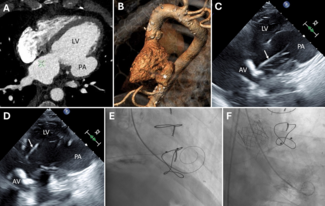

Paula Vela Martín, MD; Kristian Rivera, MD; Laura Esteban Lucía, MD; Juan Francisco Oteo Domínguez, MD

A 64-year-old woman with surgical aortic valve replacement using a Mitroflow bioprosthesis (LivaNova) 9 years prior presented with prosthetic valve dysfunction. Because of elevated surgical risk, she underwent valve-in-valve transcatheter...